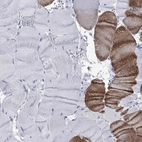

Immunohistochemistry analysis in human skeletal muscle and pancreas tissues using Anti-KLHL33 antibody. Corresponding KLHL33 RNA-seq data are presented for the same tissues.